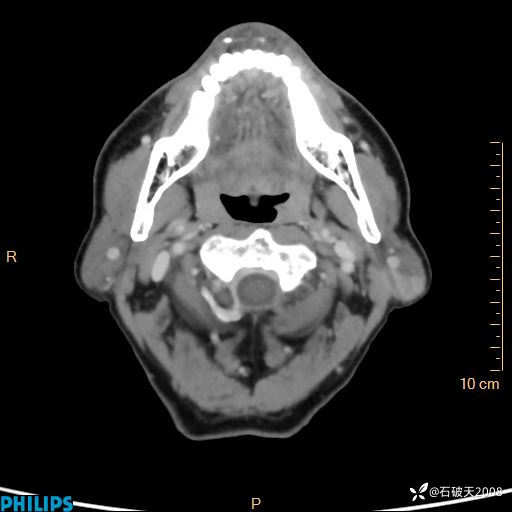

病例分享:老年男性,颈部占位,一周后公布病理

胡志勇HZY 达人已点赞男 61岁 主 诉:发现左侧面部肿物1年余。

现病史:患者于1年余前无意间发现左侧耳下有一肿物,大小如“花生米样”,无压痛,无明显红肿,无畏寒、发热,无咳嗽、咳痰,无盗汗、心慌,无手足颤动、胸闷及性格改变,未在意,未给予特殊处理,2天前至我院行彩超示: 左侧腮腺内低回声(考虑肿大淋巴结),现患者为求进一步诊治,遂来我院就诊,门诊以“局部肿物”为诊断收住我科。自发病来,患者神志清,精神可,饮食睡眠尚可,大小便正常,近期体重无下降。

动脉期